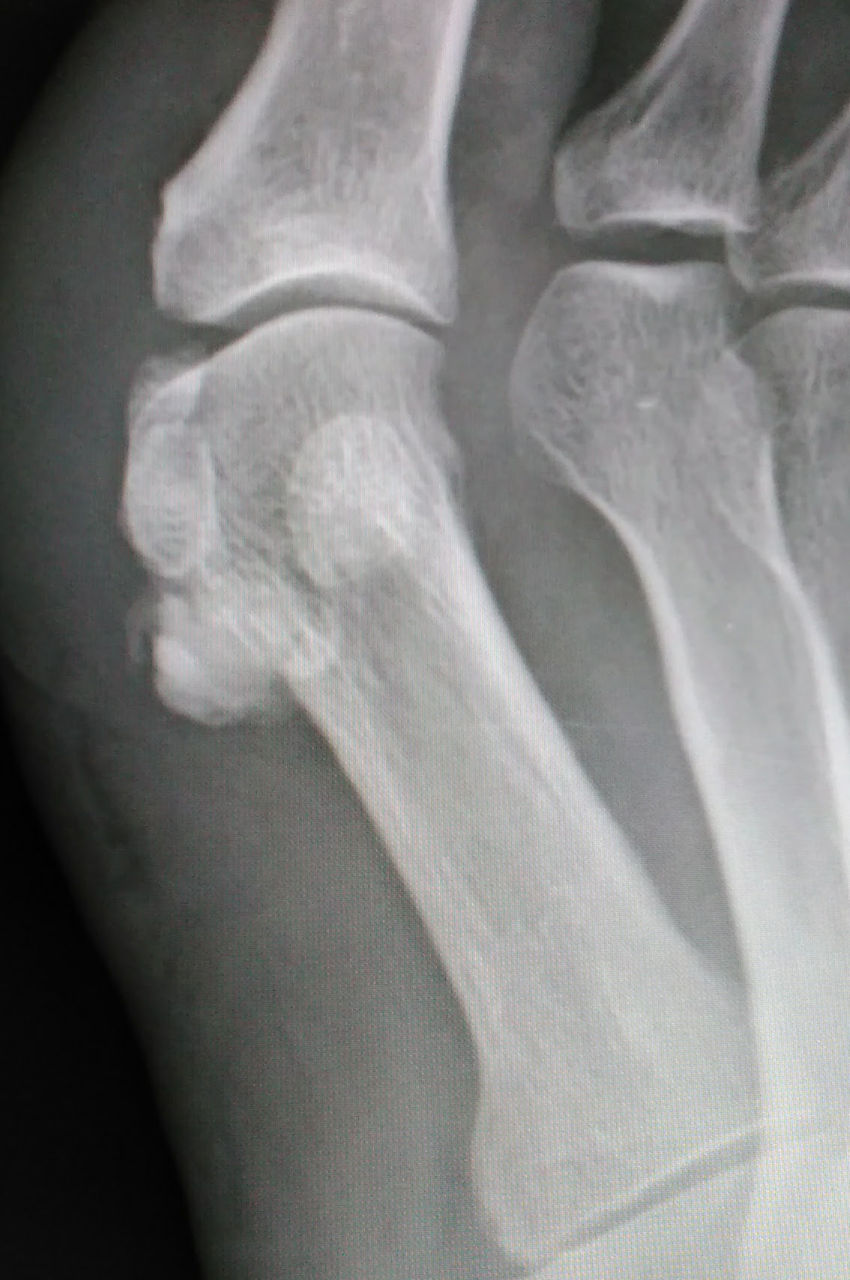

何の疑いもなく「痛風ですね」と言いそうになって、単純X線像を見てハッと息を飲みました。それが下の画像です。

正面像で2つの種子骨の下に何かクルミのような像を認めます。ただ、正面像では正直に言って見逃しかけました。

しかし、斜位像では、種子骨よりも中枢側にはっきりとした石灰沈着象を認めます。これは、痛風ではないかもしれない・・・。

足部の側面像を撮影して、確定診断にいたりました。長母趾屈筋腱に発生した石灰沈着性腱炎です。う~ん、痛風発作と非常に紛らわしい。